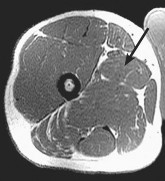

Prepare for the Arab Orthopaedic Board exam with high-yield MCQs, clinical cases, and comprehensive review materials.